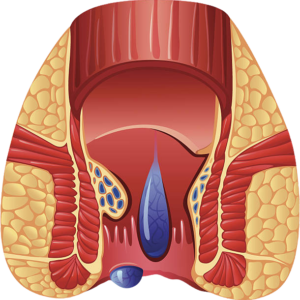

piles

PILES KILLER DROP

Piles killer Drops Relieves Painful, Bleeding and Burning Piles and Anal Fissures, Shrinks